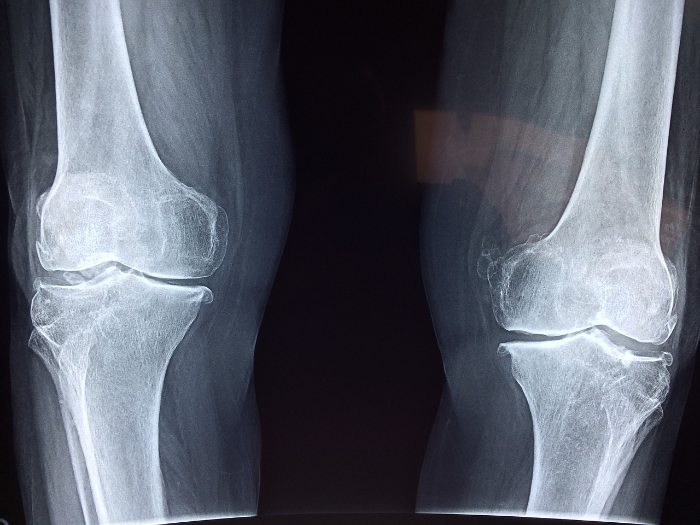

무릎 관절염 자가진단표

| 증상 | 체크 |

| 무릎이 시큰거린다 | |

| 무릎에서 발열감이 느껴진다 | |

| 앉았다 일어설때 통증이있다 | |

| 무릎주면부종이 생긴다 | |

| 다리를 굽혔다 펼때 '딱' 소리가난다 | |

| 무릎이 잘 펴지지않는다 | |

| 무릎이 무겁고 뻣뻣한 느낌이든다 | |

| 계단을 오르내릴때 통증이 있다 | |

| 무릎에서 삐걱거리는 느낌이 든다 | |

| 조금만 걸어도 무릎주위가 붓는다 |

※ 3가지 이상 해당된다면 무릎관절염을 의심해야한다.